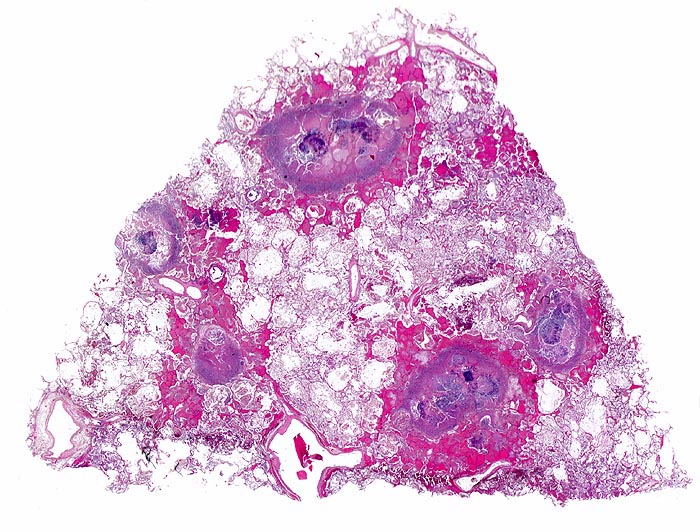

PathoPic – image database / PathoPic ID 4821 - Aspergilluspneumonie

Aspergilluspneumonie

Multiple Herde mit zentraler Nekrose und hämorrhagischem Randsaum mit Fibrinexsudaten. Im Zentrum der Herde sind Pilzmyzelien nachweisbar.

Seit 14 Monaten bekannte chronische lymphatische Leukämie behandelt mit Chemotherapie. Der Patient entwickelt unter Therapie eine Pneumonie und verstirbt an einer Pilzsepsis.